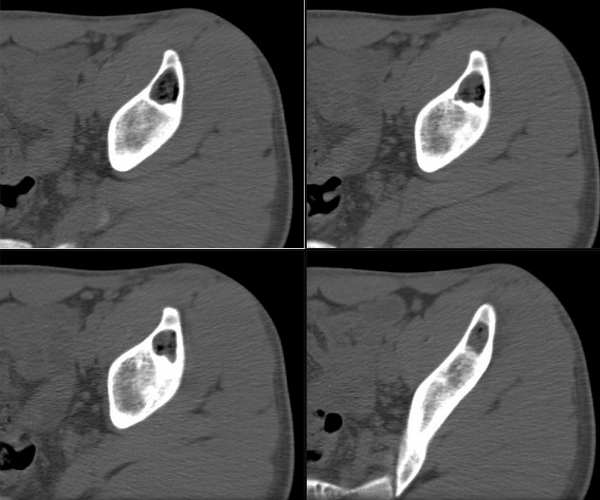

男性,19,左侧髋部疼痛两周。病变ct值有软组织及脂肪密度影。

影像表现:左侧髂骨内卵圆形囊性低密度灶,病灶内为脂肪密度及软组织密度;周围骨质似有轻度硬化带,局部骨皮质完整、光滑;未见骨膜下新生骨。

意见:骨良性病变,考虑为骨脂肪瘤。

骨肿瘤或者肿瘤样变的病灶中出现脂肪密度的有:骨脂肪瘤,骨脂肪肉瘤,骨囊肿等

骨囊肿内多为液性密度,也可含有少量胆固醇成分或者肉芽组织成分,本例病灶内脂肪成分较多,不含液性成分;脂肪肉瘤病灶为恶性浸润征象多见,也可见有钙化征象。

定位:左髂骨

征象:囊状低密度病灶,边缘清楚、光整,有薄层硬化边缘,其内密度不均,可见液平面。无明显骨膜增生和软组织异常。

定性:良性

1、骨囊肿:多见于20岁以下青少年,病变为单囊或多囊,其内通常可见骨性或软组织间隔,骨折时可有液性密度影,也可含少量脂质,应首先考虑。

2、动脉瘤样骨囊肿:好发于年轻人,病灶一般膨胀明显,密度不均,包括软组织影、液体密度影,偶尔有斑片状钙化影,不能排除。

3、骨脂肪瘤:少见,多见于中年人,病灶内常有钙化或骨化影,因伴有其他不同成分使得脂肪含量变化较大,一般没有液体影像,可能性不大。

左侧髂骨内卵圆形囊性低密度灶,病灶内为脂肪密度及软组织密度;周围骨质似有轻度硬化带,局部骨皮质完整、光滑;未见骨膜下新生骨。图像上髂骨周围软组织未见确切异常。

考虑骨良性病变,骨脂肪瘤可能性大。其他待排。